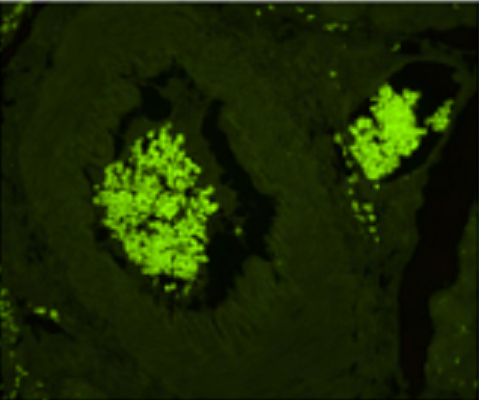

![]() |

| 上图为人胰腺组织染色结果:绿色为insulin的染色。左图为未经任何处理的染色结果,右图为使用TrueVIEW Treatment Mounted with Vibrance + 3x DAPI(SP-8500)试剂盒染色结果。与未经处理的染色结果相比,经该试剂盒处理后,自发荧光显著减少,核染色显著增强。 | |